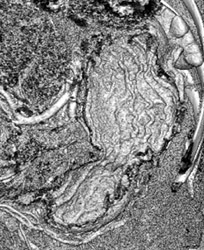

Normal Gastric Folds